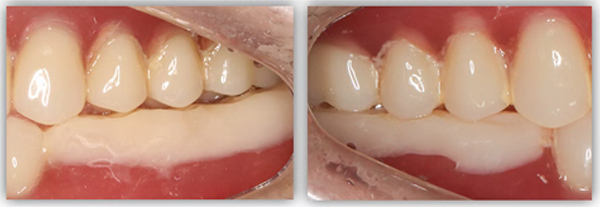

我决定做难但正确的事情。种植手术完成后,我让患者戴上了树脂义齿重建咬合,让他通过日常的咀嚼,在原本平整的下牙义齿上慢慢形成新的尖窝对应关系。前后花了半年时间,才达到稳定且可重复的咬合状态。这时候,再制作第二幅临时义齿,也就是有解剖牙尖和尖窝交错关系的临时牙,让患者再次适应咬合3个月。最后,我把患者适应并且满意的咬合关系转移到他的最终牙冠上,完成了修复治疗。

这位患者不到60岁,但由于后牙全部缺失多年,残留的前牙已松动且上下无法接触,他基本没办法正常咀嚼,人非常消瘦。完成治疗后我跟踪了这个病例一年,从前后对比照片可以看出,能正常吃东西后他的脸上渐渐也有肉了。